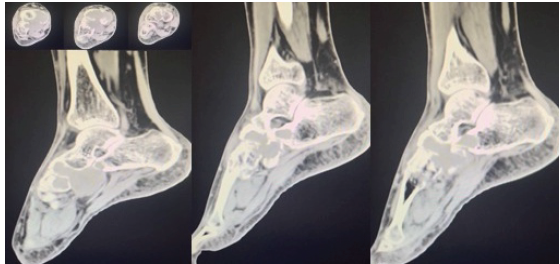

Routine radiological investigations revealed a large globular lesion in the navicular bone (Fig. 2). Computed tomography scan (Fig. 3, 4) and magnetic resonance imaging (Fig. 5) modalities revealed an expansile lesion in the navicular bone lobulated extension of lesion on the plantar aspect and adjacent tarsal bones (cuneiform, cuboid) and intertarsal joints. We thus had a suspicion of a malignant lesion? Round cell tumour? Ewing’s sarcoma. On following up with histopathology, the histopathological report of lesion determined giant cell tumor (GCT).

Figure 3: Computed tomography scan shows expansile lesion.

Figure 4: Computed tomography scan shows expansile lesion.